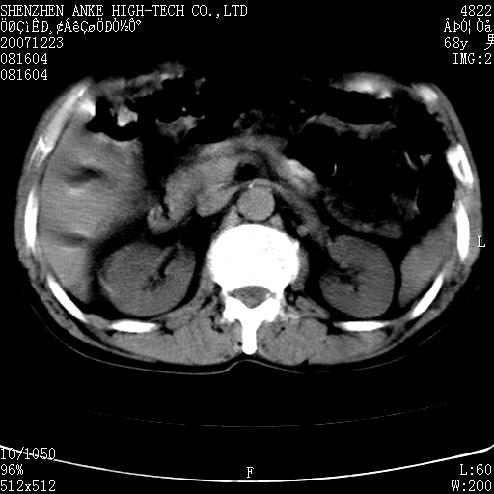

患者:男,63岁,2年前胆囊切除术后,现右上腹部剧烈疼痛近2天.

有无外伤史?右肾包膜下血肿可疑。

主要是问右肾有没有问题?患者无明显外伤史.

未见异常,病人差闭气,伪影较多.

肠道准备不好,干扰影大。

肠道气体伪影干扰太大了,应该是干扰所致,未见明显异常。

肠道准备不好,胃底后壁显示不清,右肾改变考虑为伪影。

上腹部ct平扫未见明显异常。(肠道气体较多,患者呼吸了)